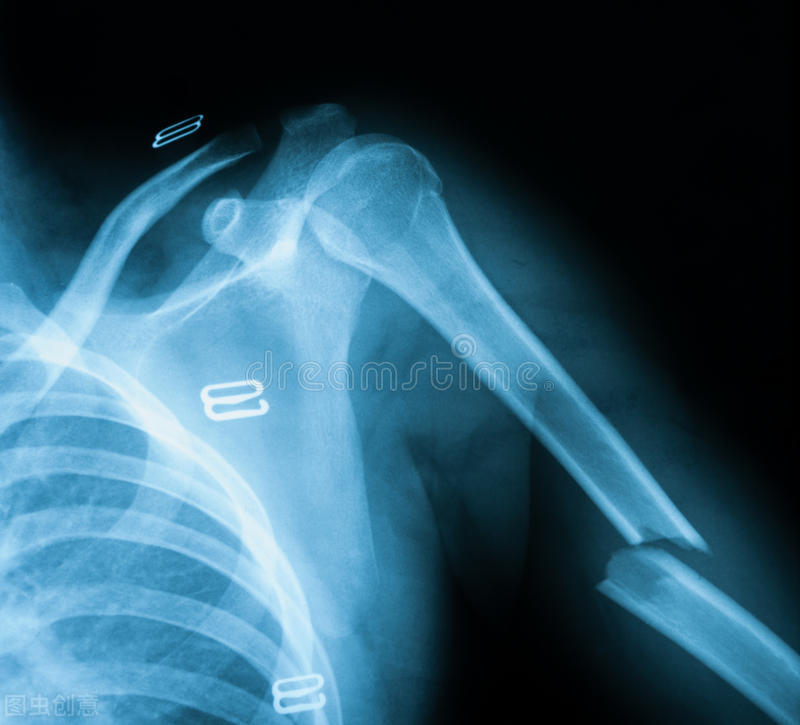

大学生都能骨质疏松,可能很多人觉得很不可思议,而实际上确实发生了这样的问题。前段时间的一个病例,大二男生和室友掰手腕,突然咔吧一声,剧痛无比,来我们医院一查,前臂骨折了,而X线片上发现骨皮质非常薄,再一查骨密度,还是明显的骨质疏松。这个小伙子,平时没有任何运动爱好,不打球也不游泳,最爱宅宿舍,熬夜打游戏,从不喜欢喝牛奶,也不喜欢豆制品。

然后,掰手腕引起的骨折,篮球足球运动中小腿骨折,剧烈*力暴**引起,都不能称为脆性骨折。例如NBA球星保罗乔治比赛中,落地剪切力过大,小腿胫腓骨骨折,还有前段时间UFC综合格斗比赛中,一名选手惨遭断腿,他们作为顶级运动员,每天坚持锻炼,不可能有骨质疏松,所以这种情况下的突发意外骨折,哪怕是自己主动发力引起的,也不属于骨质疏松性骨折。脆性骨折发生在腕部、肩部、髋部和脊柱。例如桡骨远端骨折、肱骨近端骨折、股骨近端骨折、椎体压缩性骨折等。